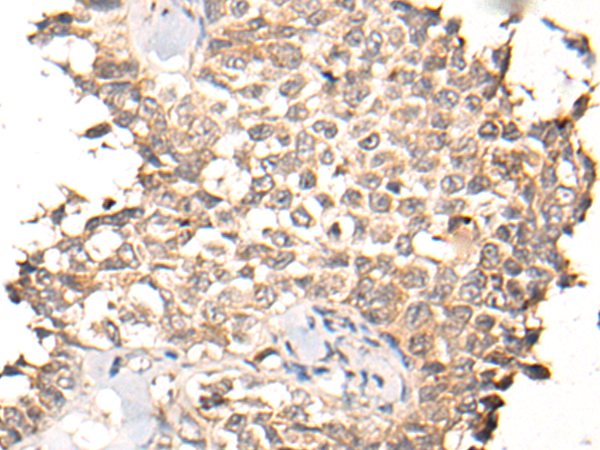

IHC positive control:

Human thyroid cancer and human ovarian cancer